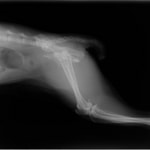

ペルシャ猫 11ヶ月齢 雄

他院にて左大腿骨遠位の成長板骨折(salter-harrisⅠ型)が認められており、治療相談を目的として来院。当院にて、キルシュナーワイヤーを用いたピンニングにより骨折部位の整復を行いました。術後の経過は良好で、現在も経過観察中です。

術前レントゲン

術後レントゲン